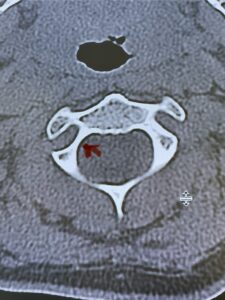

Fig. 2b: Axial CT scan of the brain demonstrating the thickness of the midline keel (red arrow) compared to the more lateral subocciput (red dot) making the keel ideal place for screw fixation